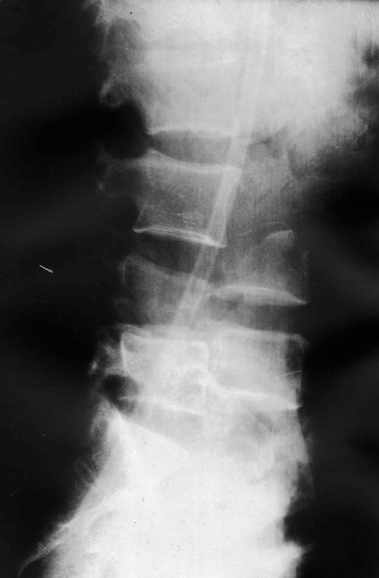

Высылаю рентгенограммы. Спасибо за рекомендации. Наша тактика согласуется с вашими рекомендациями за исключением транспедикулярной фиксации - у данного пациента на наш взгляд предпочтительнее наружная транспедикулярная фиксация (Курганский аппарат). Погружная конструкция предпологает одномоментную репозицию до выполнения забрюшинного доступа и ревизии переломов что теоретически может привести к повреждению дурального мешка и корешков. АВФ позволит восстановить ось позвоночника и смещение по длине непосредственно под контролем глаза на этапе внебрюшинного доступа. Сколько сегментов замыкать? Я думаю может потребоваться замкнуть и сегмент L2-L3. Предполагается использовать тело L4 для костной пластики таким образом, чтобы ширина спиномозгового канала на уровне оперированных сегментов была увеличена. Фиксация тел позвонков вентральной пластиной.